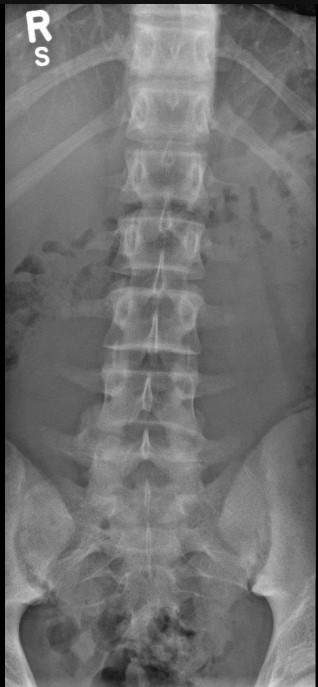

Normal Images Cervical Spine Lateral Xray Cervical Spine CT Cervical Spine MRI Sagittal Cervical Spine MRI Axial Lumbar Spine AP Xray Lumbar Spine Lateral Xray Lumbar Spine CT sagittal Lumbar Spine MRI sagittal Lumbar Spine MRI axial